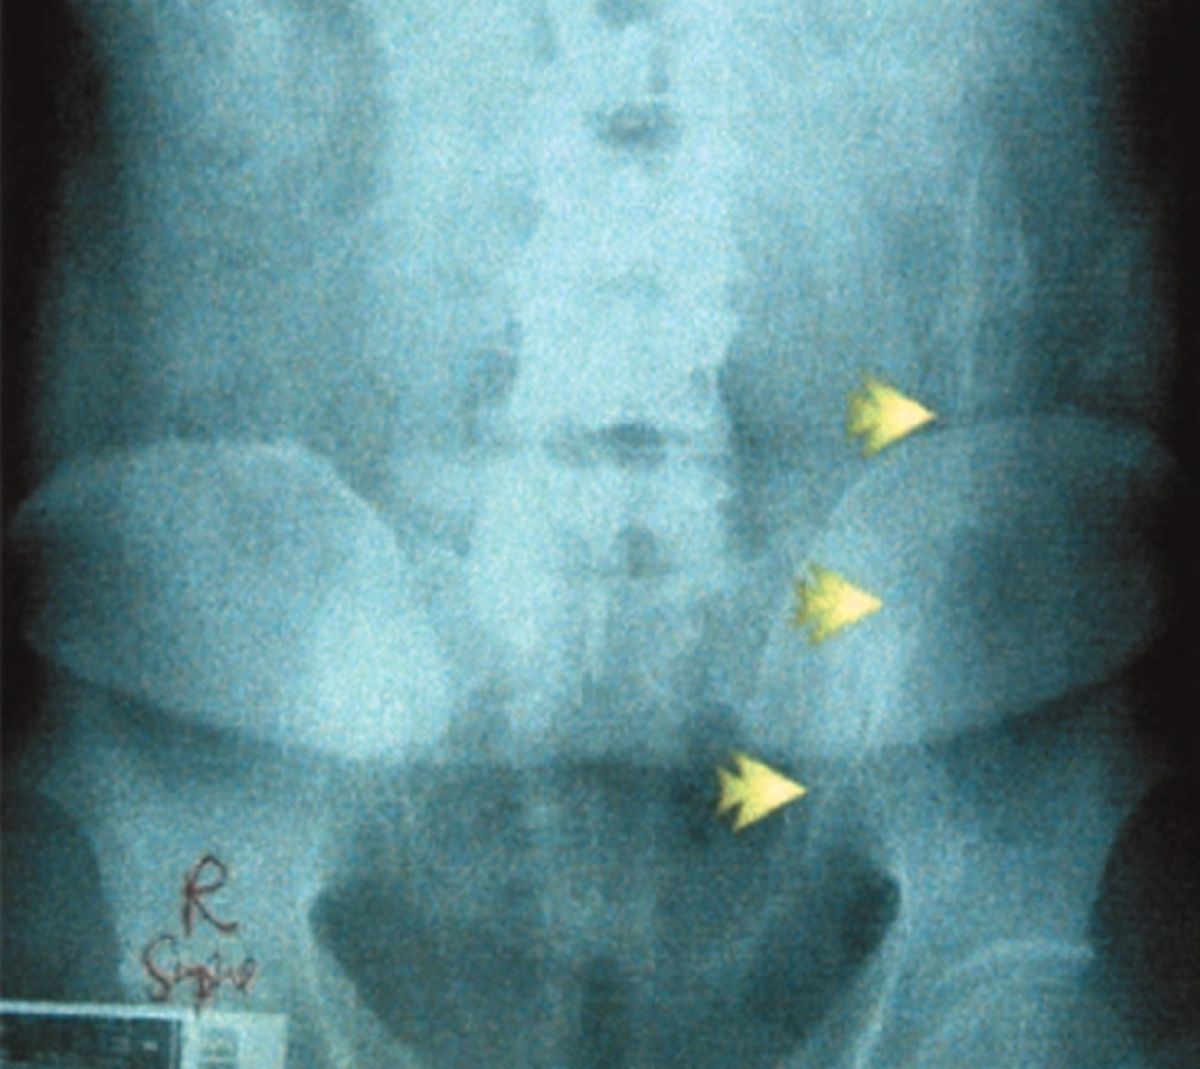

Lekarze, do których przyszli ci pacjenci na pewno nie mogli uwierzyć w to, co zobaczyli na zdjęciach. Jeszcze dziwniejsze były tłumaczenia. Ten pacjent, u którego znaleziono butelkę tłumaczył, że potknął się w okolicach śmietnika i naczynie samo dostało się do jego odbytu.